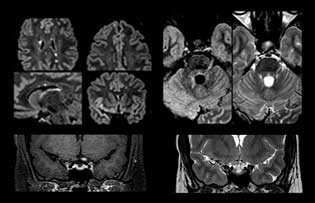

Multiple sclerosis imaging requires precision, speed

When multiple sclerosis (MS) is suspected, clinicians need a diagnosis early on, so treatment can begin as soon as possible. “A challenge for imaging is that MS lesions in the brain and spine may be very small,” says Dr. Savatovsky. “We need precise imaging to tell exactly where the lesion is, so we need high quality, very high resolution images, preferably in 3D[1]. We need to know if a high T2 signal intensity is suggestive of MS or just aspecific. And we want to visualize active lesions very well.”

Imaging MS in brain

For MS imaging in the brain, Dr. Savatovsky uses 3D FLAIR as the basic sequence to visualize the lesions and assess the situation and lesion load. “We count the lesions in each location to determine if the criteria of the disease are fulfilled. We use a T2-weighted sequence because our neurologists are used to it. We compare the lesion load on FLAIR with a 3D T1 post-contrast sequence to help us determine whether lesions are old or new. We typically administer the contrast before the patient enters the machine because it shortens the examination time and allows to visualize active lesions that tend to be more visible after several minutes. When a differential diagnosis is difficult, we add sequences such as susceptibility imaging, because some focal MS lesions have a small vein in the center[3].”

MS imaging in spine is more complicated

“For MS imaging in the spine, the basic examination includes a sagittal T2 and a post-contrast sagittal T1-weighted sequence in the whole spine. These are done in two stacks and using thin slices, for example 2 mm, without gap. As in the brain, the T2-weighted sequence visualizes the overall lesion load and helps determine if lesions are old or new. The post-contrast T1- weighted sequence helps in assessing if a lesion is new. We will sometimes add a T1 inversion recovery sequence, which has very good sensitivity, if we don’t find any lesions on T2,” Dr. Savatovsky says. “Additionally, if there is contrast enhancement outside the spine, it’s usually not MS but another kind of inflammation.”